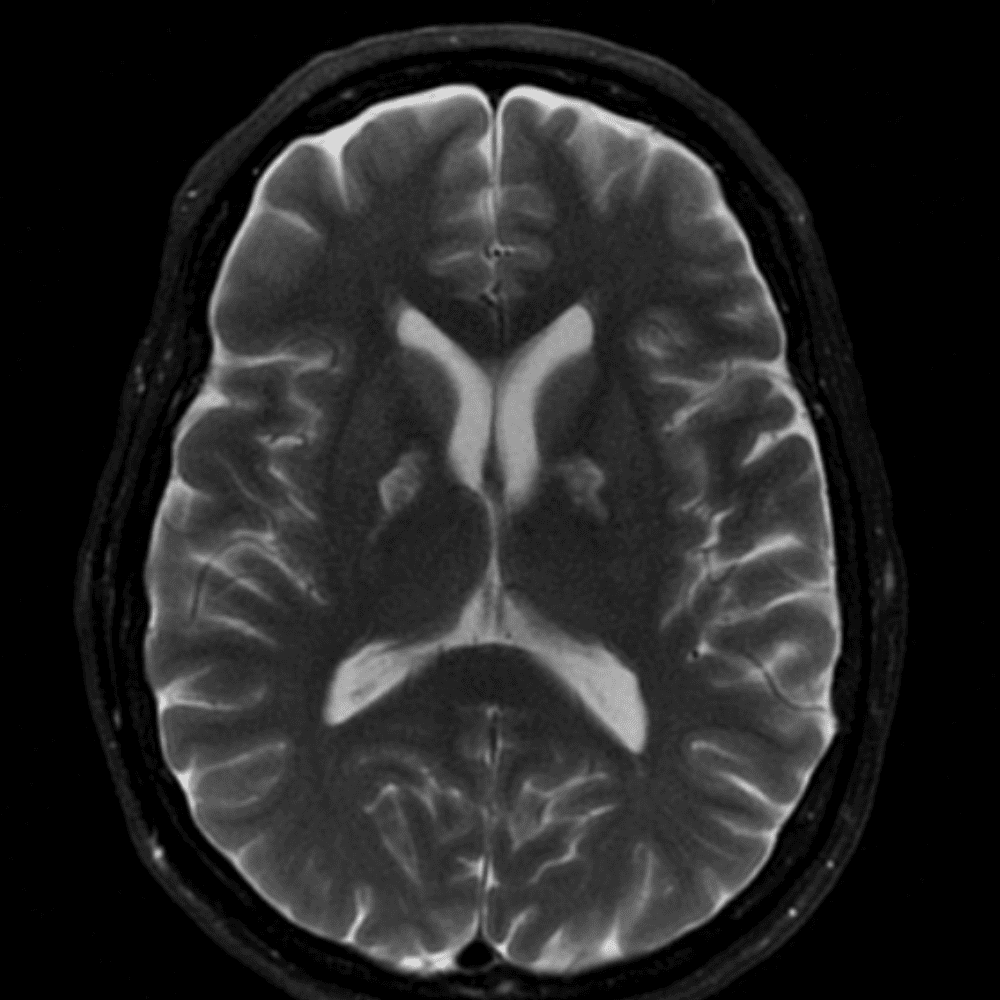

๋‹น์ง ์‹œ ํ”ํžˆ ๋ณผ ์ˆ˜ ์žˆ๋Š” ์‚ฌ๋ก€์˜ ์ „ํ˜•์ ์ธ ์˜ˆ๋ฅผ ํฌํ•จํ•ฉ๋‹ˆ๋‹ค.

39 ์‚ฌ๋ก€

์—ฐ์Šต

๋ฏธ๋ฌ˜ํ•˜๊ฑฐ๋‚˜ ์–ด๋ ค์šด ์‚ฌ๋ก€์™€ ์ผ๋ถ€ ์ •์ƒ ์‚ฌ๋ก€๋ฅผ ํฌํ•จํ•˜์—ฌ ๋‹น์ง์„ ์‹œ๋ฎฌ๋ ˆ์ด์…˜ํ•ฉ๋‹ˆ๋‹ค.

50 ์‚ฌ๋ก€